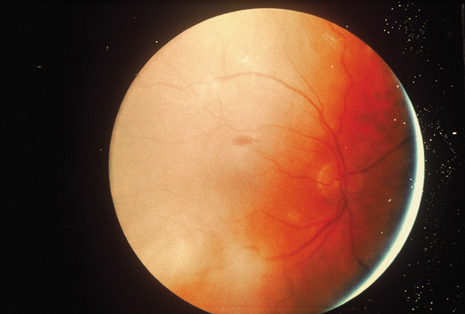

Although keratocentesis had been advocated historically as a treatment for active uveitis, it lost the attention of ophthalmologists until 1919, when Bruckner3 first examined the aqueous humor for diagnostic purposes. Laboratory techniques were revolutionized in the 20th century in areas such as: (a) evaluating very small aliquots of fluid (0.2 to 0.3 mL of aqueous or vitreous), and (b) identifying specific microbial organisms and the predominance of other cell types, antibodies, and proteins in these fluids (Figs. 1, 2, 3, 4, 5, and 6). These advancements have led to the development of diagnostic paracentesis for sight-threatening ocular inflammations that are difficult to diagnose. Witmer4 and O'Connor5 have provided strong evidence that samples of the aqueous humor reflect the antibody-producing capabilities of the iris and ciliary body, particularly when more specific antibody per unit of gamma globulin can be found on the aqueous humor than in the blood of the same patient.6–8 These determinations may be highly significant when one considers the fact that diseased tissue is being bathed in an antibody-containing fluid that is elaborated locally. For instance, in the case shown in Figure 1, the immunofluorescent antibody titer to toxoplasmosis is four times greater in the vitreous aspirate at the time of vitrectomy for repair of retinal detachment than in the plasma. These same considerations have long been recognized in syphilis of the central nervous system, wherein specific antibodies may be present in the cerebrospinal fluid but not in the blood. This is also the case with an unusual presentation of ocular coccidioidomycosis9 or toxocariasis.